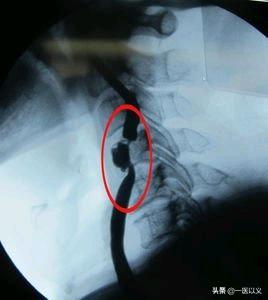

上の頸部のCTA血管造影は、右内頸動脈の限局性狭窄を示す。